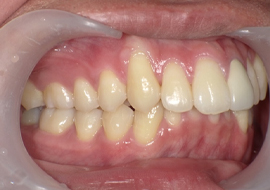

症例7

Before

After

| 主訴 | 上の1-1の隙間気になる |

|---|---|

| 年齢 | --- |

| 治療 期間 |

約3年8ヶ月 |

| 治療 内容 |

インビザラインコンプリヘンシブ ラミネートべニア、ジルコニア補綴 |

| 治療費 | ¥1,925,000(税込)/調整料含む |

| 治療のリスク | 歯を動かすことで、歯茎が下がるリスクある。 矯正終了後は、リテーナーを使用し、後戻りを防ぐ必要がある。 |